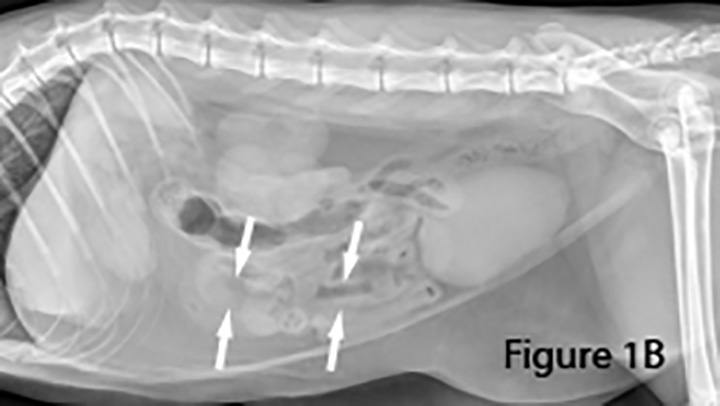

Imaging Intestinal Obstruction Clinician s Brief

Bowel Obstruction Intestinal Blockage in cats PDSA top, Gastrointestinal Foreign Bodies FB In Dogs Cats top, Intestinal obstruction in cats Veterinarian Karlsruhe Small Animal Center Arndt top, Please read my baby is suffering from blocked intestines. guide me what to do. r CATHELP top, Intestinal Blockage in Cats PetMD top, Constipation in Cats VCA Animal Hospitals top, Please read my baby is suffering from blocked intestines. guide me what to do. r CATHELP top, What To Do If Your Cat Swallows a String top, Burmese and pica Ace and his intestinal obstruction Perth Cat Hospital top, Imaging Intestinal Obstruction Clinician s Brief top, Arizona Veterinary Emergency Critical Care Center Gilbert AZ Pets can be curious and sometimes that leads to swallowing indigestible objects which can result in bowel or gastrointestinal obstruction.... top, What happened to my cat Virus caused intestinal blockage. r vet top, Cat Intestinal Blockage Surgery Cost Recovery Berkeley Vets top, Abdomen cat. Abdominal radiographs revealed marked gas distention of. Download Scientific Diagram top, Intestinal Blockage in Cats Vet Reviewed Signs Causes Treatment Catster top, Bowel Obstruction Intestinal Blockage in cats PDSA top, Intestinal Blockage Surgery For Cats Tigard Vet top, A Visual Guide to GI Obstruction on Radiographs top, Identifying Mechanical Obstruction on Radiographs MSPCA Angell top, Cat Intestinal Blockage Surgery Danbury Vet top, Bowel Obstructions in Dogs Cats Erin Vets top, Cat with Bowel or Intestinal Obstruction X ray Image or Radiography. Medical Imagery Stock Photo Image of science spine 172369032 top, Cat Intestinal Blockage Surgery Cost Recovery Farmington Hills Angel Animal Hospital top, Imaging Intestinal Obstruction Clinician s Brief top, Hairballs Can be Dangerous The Animal Medical Center top, Cat Has Hairball Why What To Do Dutch top, Cat Intestinal Blockage Surgery Cost Recovery Seattle Vets top, Vomiting in Cats What Causes It and How to Help BetterVet top, Cat Intestinal Blockages Surgery Matthews Veterinary Internal Medicine top, Cat With Bowel Or Intestinal Obstruction Xray Image Or Radiography Medical Imagery Cat Anatomy With Spine Tail And Rib Cage Bones Or Skeleton Stock Photo Download Image Now iStock top, How to diagnose and treat the chronic and acute vomiting top, entrodorsal radiograph of a cat after barium administration showing. Download Scientific Diagram top, CAT BOWEL OBSTRUCTION X RAY Stock Image Image of radiography veterinary 30050835 top, Cats Hairballs a normal and natural phenomenon baci top, Intestinal Obstruction top.

Bowel Obstruction Intestinal Blockage in cats PDSA top, Gastrointestinal Foreign Bodies FB In Dogs Cats top, Intestinal obstruction in cats Veterinarian Karlsruhe Small Animal Center Arndt top, Please read my baby is suffering from blocked intestines. guide me what to do. r CATHELP top, Intestinal Blockage in Cats PetMD top, Constipation in Cats VCA Animal Hospitals top, Please read my baby is suffering from blocked intestines. guide me what to do. r CATHELP top, What To Do If Your Cat Swallows a String top, Burmese and pica Ace and his intestinal obstruction Perth Cat Hospital top, Imaging Intestinal Obstruction Clinician s Brief top, Arizona Veterinary Emergency Critical Care Center Gilbert AZ Pets can be curious and sometimes that leads to swallowing indigestible objects which can result in bowel or gastrointestinal obstruction.... top, What happened to my cat Virus caused intestinal blockage. r vet top, Cat Intestinal Blockage Surgery Cost Recovery Berkeley Vets top, Abdomen cat. Abdominal radiographs revealed marked gas distention of. Download Scientific Diagram top, Intestinal Blockage in Cats Vet Reviewed Signs Causes Treatment Catster top, Bowel Obstruction Intestinal Blockage in cats PDSA top, Intestinal Blockage Surgery For Cats Tigard Vet top, A Visual Guide to GI Obstruction on Radiographs top, Identifying Mechanical Obstruction on Radiographs MSPCA Angell top, Cat Intestinal Blockage Surgery Danbury Vet top, Bowel Obstructions in Dogs Cats Erin Vets top, Cat with Bowel or Intestinal Obstruction X ray Image or Radiography. Medical Imagery Stock Photo Image of science spine 172369032 top, Cat Intestinal Blockage Surgery Cost Recovery Farmington Hills Angel Animal Hospital top, Imaging Intestinal Obstruction Clinician s Brief top, Hairballs Can be Dangerous The Animal Medical Center top, Cat Has Hairball Why What To Do Dutch top, Cat Intestinal Blockage Surgery Cost Recovery Seattle Vets top, Vomiting in Cats What Causes It and How to Help BetterVet top, Cat Intestinal Blockages Surgery Matthews Veterinary Internal Medicine top, Cat With Bowel Or Intestinal Obstruction Xray Image Or Radiography Medical Imagery Cat Anatomy With Spine Tail And Rib Cage Bones Or Skeleton Stock Photo Download Image Now iStock top, How to diagnose and treat the chronic and acute vomiting top, entrodorsal radiograph of a cat after barium administration showing. Download Scientific Diagram top, CAT BOWEL OBSTRUCTION X RAY Stock Image Image of radiography veterinary 30050835 top, Cats Hairballs a normal and natural phenomenon baci top, Intestinal Obstruction top.